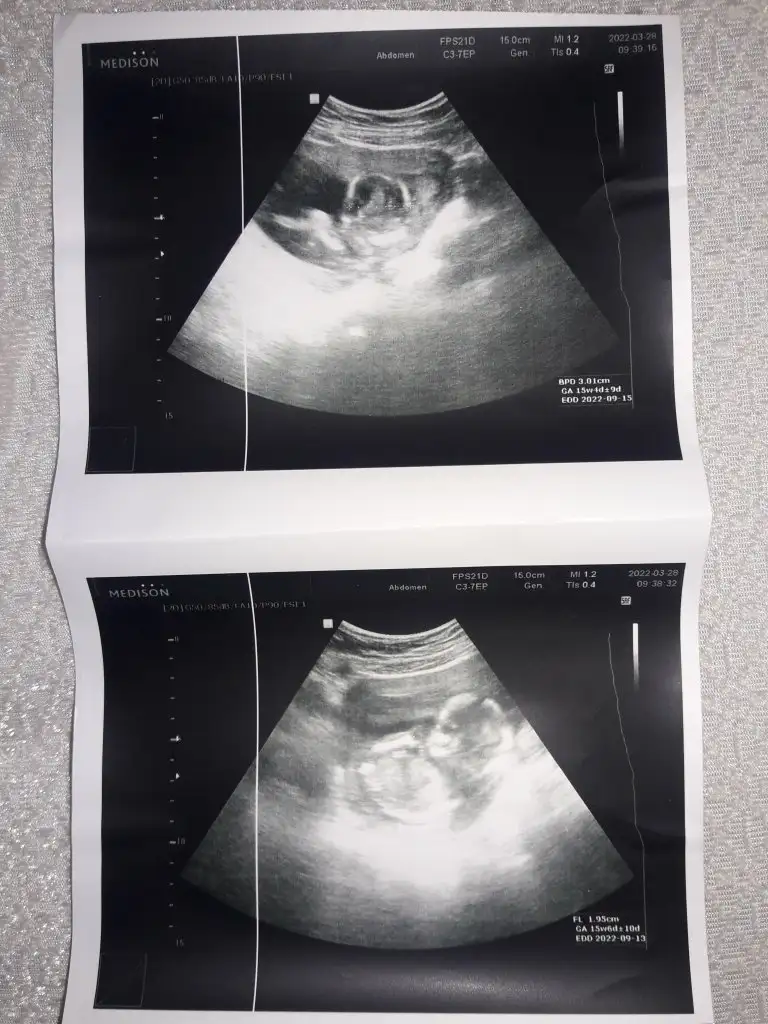

Kuzucum evet erkek gibi bir pozisyonu var ama görüntü çok silik.Merhaba iki gün öncemi ne 12 haftalık ultrason görüntümü atmıştım kıza benziyor dediniz bugünde üçlü test için özler gittik ultrason ile karından baktı bacaklarını acmamisti ama sonradan erkeğe benzediğini söyledi haftaya kendi doktorum söylicem siz ne düşünüyorsunuz

Evet çok silik ama bide size paylaşmak istedim haftaya perşembe kontrolüm var çikolata yiyip gideyim bari kendi doktorum soylicegini söylemişti çikolatadan başka ne yapabilirimKuzucum evet erkek gibi bir pozisyonu var ama görüntü çok silik.